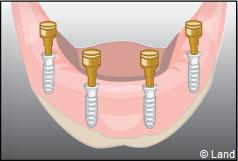

Les implants peuvent aussi servir à stabiliser un appareil amovible au maxillaire supérieur comme au maxillaire inférieur. Dans ce cas, les implants retiennent la prothèse amovible par des systèmes d’attachement.

Deux techniques sont possibles. Elles font appel à la barre de rétention ou aux boutons-pressions.

Exemple d’une réhabilitation complète implantaire

Situation clinique initiale

Situation clinique terminée